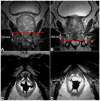

Methods and materials: This retrospective study included 108 men (median age, 64 years; range, 43-87 years) who received external-beam radiotherapy (EBRT) and/or brachytherapy for PCa and underwent endorectal-coil MRI of the prostate within 180 days before RT and a median of 20 months (range, 2-62 months) after RT. On all MRIs, two readers independently measured the urethral length (UL) and graded the margin definition (MD) of the urethral wall and the signal intensities (SIs) of the urethral wall and pelvic muscles on 4-point scales.

Results: The mean urethral length decreased significantly from pre- to post-RT MRI (from 15.2 to 12.6mm and from 14.4 to 12.9 mm for readers 1 and 2, respectively; both p-values <0.0001). Brachytherapy resulted in greater urethral shortening than EBRT. After RT, SI in the urethral wall increased in 57% (62/108) and 35% (38/108) of patients (readers 1 and 2, respectively). The frequency and magnitude of SI increase in pelvic muscles depended on muscle location. In the obturator internus muscle, SI increased more often after EBRT than after brachytherapy, while in the periurethral levator ani muscle SI increased more often after brachytherapy than after EBRT.

Conclusion: After RT for PCa, MRI shows urethral shortening and increased SI of the urethral wall and pelvic muscles in substantial percentages of patients.